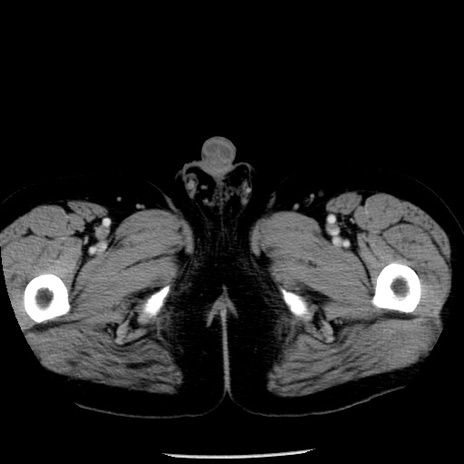

症例29(横断像)

【症例】40歳代男性

【現病歴】2日前から胃痛あり。徐々に周期的な激痛に変化した。本日になっても激痛があるため受診。

【身体所見】意識清明、BT 38-39℃台あり、腹部:膨満、やや硬、右下腹部に圧痛あり。

【データ】WBC 8500、CRP 23.26